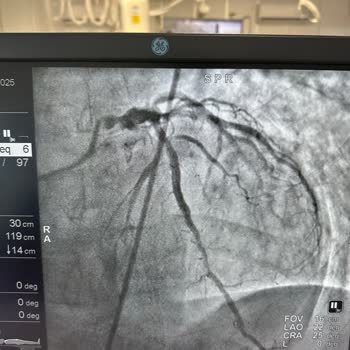

anjiyo